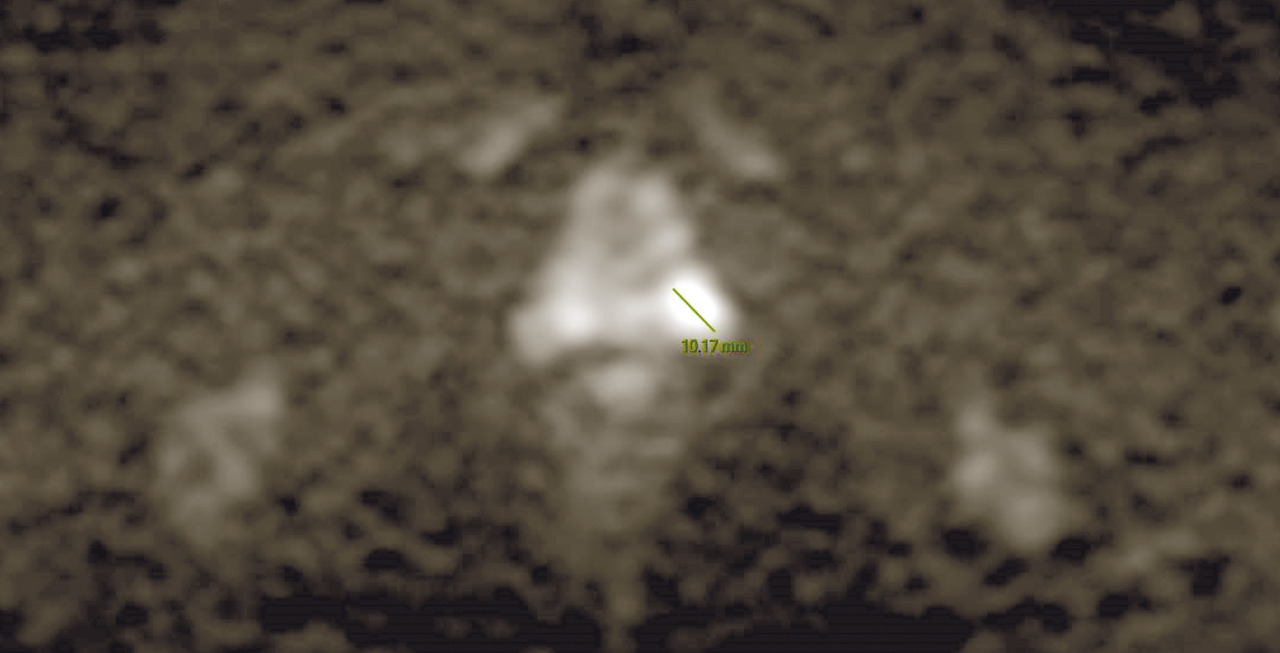

L’IRM multiparamétrique (IRM-mp) de la prostate joue un rôle fondamental dans la détection du cancer de la prostate : le protocole multiparamétrique, qui prévoit des séquences anatomiques en T2, T1 en perfusion (dynamic contrast-enhanced magnetic resonance imaging, DCE-MRI) et en diffusion (diffusion weighted imaging, DWI), est en mesure de fournir une combinaison d’informations anatomiques, biologiques et fonctionnelles nécessaires pour une définition plus précise des lésions suspectes (fig. 1 et 2).

À ce jour, avec la diffusion d’outils de plus en plus sophistiqués et précis pour effectuer des biopsies avec fusion d’images entre l’IRM multiparamétrique et l’échographie transrectale en temps réel, la biopsie avec connaissance de l’anatomie prostatique sur la base des images d’IRM réalisée sous guidage échographique est devenue une approche indispensable, permettant de faire évoluer les biopsies systématisées, réalisées « à l’aveugle», vers des biopsies ciblées. De nombreuses études ont montré que l’échantillonnage ciblé, en plus de l’approche systématique, est mieux corrélé au score de Gleason pathologique, tandis que d’autres ont montré une meilleure performance en termes de sensibilité et de spécificité de la biopsie ciblée par rapport à la réalisation des biopsies avec approche systématique, réduisant de manière significative le taux de détection des tumeurs cliniquement non significatives. Par conséquent, la réalisation de l’IRM avant de programmer les biopsies est de plus en plus recommandée afin de :

Les études menées pour l'évaluation des performances diag­nostiques du protocole multiparamétrique ont montré une sensibilité et une spécificité élevées, avec une valeur prédictive négative entre 63 % et 91 % pour les cancers de la prostate de tout grade et entre 92 et 100 % pour les tumeurs cliniquement plus significatives (score de Gleason > 6). L’IRM doit toujours être effectuée avec tous les détails concernant les valeurs de PSA (récentes et anciennes si disponibles), le toucher rectal, l’âge du patient, les comorbidités et les antécédents familiaux. L’ensemble de ces éléments peut être décisif dans la sélection des patients candidats à la biopsie, avec deux avantages assurés plus spécifiquement par l’IRM : d’une part, de réduire les biopsies inutiles d’environ 25 % et, par conséquent, de prévenir le surdiagnostic et le traitement excessif des tumeurs cliniquement indolentes, non significatives ; d’autre part, d’augmenter le taux de diagnostic de tumeurs cliniquement significatives d’environ 18 %, tumeurs qui autrement ne seraient pas diagnostiquées par les biopsies systématisées, « à l’aveugle ».

Contrairement à la tomodensitométrie (TDM), la résolution spatiale de l’image garantie par l’IRM permet d’élucider l’anatomie zonale de la glande prostatique et de distinguer la portion périphérique de la glande et le tissu néoplasique, qui a un signal intrinsèque différent. De plus, pour les mêmes raisons, l’IRM est en mesure de mieux représenter toutes les structures pelviennes restantes, avec une clarification remarquable de leurs rapports (vessie, rectum, muscles, structures squelettiques, vaisseaux). Ces caractéristiques rendent désormais l’utilisation de l’IRM multiparamétrique également essentielle à des fins de planification thérapeutique (bilan d’extension locorégional avant traitement local, par exemple de chirurgie ou de radiothérapie externe).